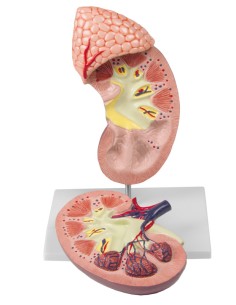

Modèle anatomique de néphron avec vaisseaux sanguins, agrandi 120 fois k10/1